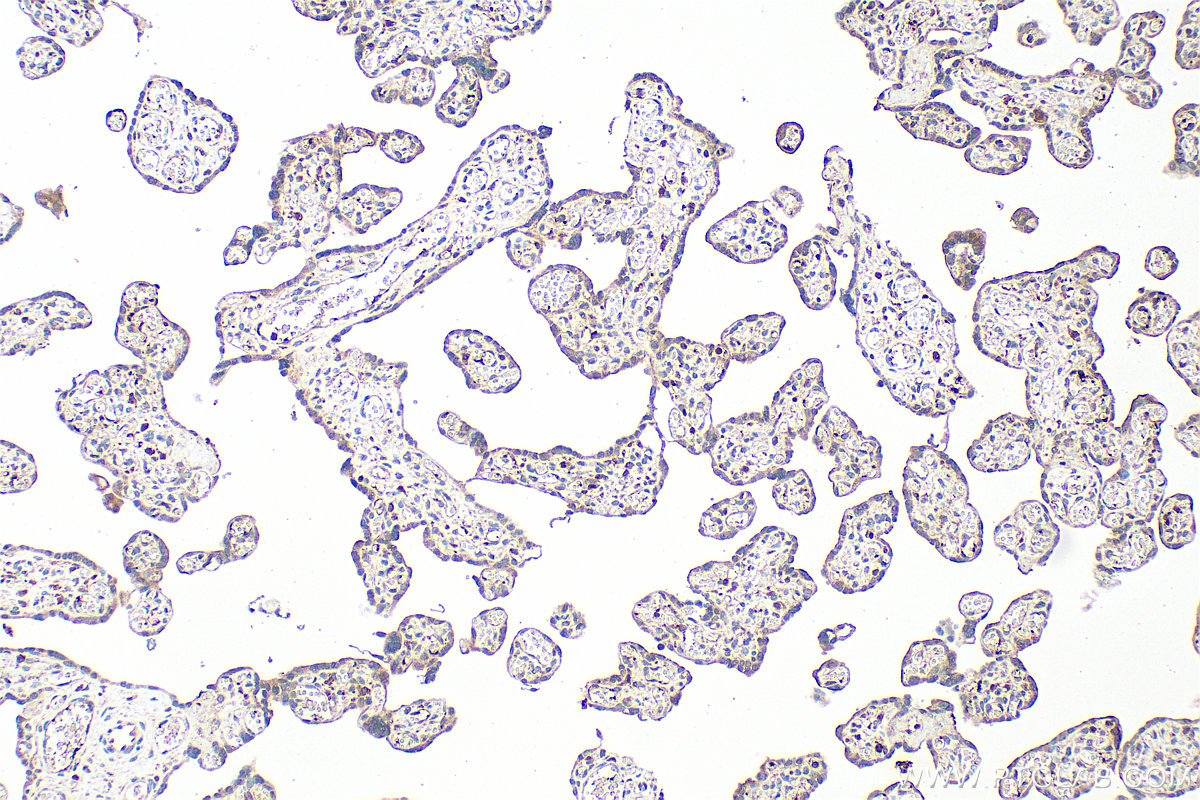

| Positive IHC detected in | mouse placenta tissue, human placenta tissue Note: suggested antigen retrieval with TE buffer pH 9.0; (*) Alternatively, antigen retrieval may be performed with citrate buffer pH 6.0 |

13313-1-AP targets CXCL7/PPBP in WB, IHC, ELISA applications and shows reactivity with human, mouse samples.

| 经测试应用 | WB, IHC, ELISA Application Description |